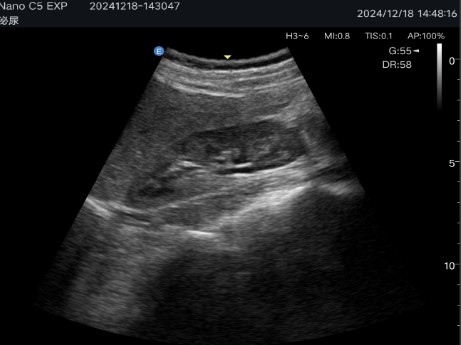

Abdominal diagnostics, obstetrics and gynecology: Allows detailed evaluation of internal organs and structures.

High-quality images: The SynSight platform provides clear images with noise reduction and optimization of details.